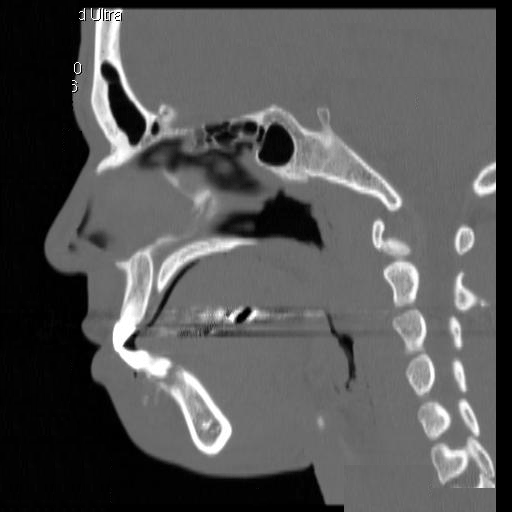

Clinical information The patient was a 23 year-old man who went to see the dentist because of dull pain, swelling of the chin,  and loosened lower front teeth. He was referred to this hospital after initial examination. A CT scan was performed and and a biopsy was taken. Representative images are presented here. Panel D is a sagittal reconstruction from axial CT scans. A resection was subsequently performed.

CT scan: On the CT scan images (Panel A, B, C, and D), two lesions are present.  There is a lesion at the mental protuberance that appears to have penetrated the cortex and invaded into the soft tissue. The patchy hyperdensity strongly suggests that this lesion has mineralize elements ( in Panel B). The border of the lesions in the mandible is poorly defined. The penetration of the bone and extension into the soft tissue is best appreciated in the sagittal reconstruction in (Panel D). These features are highly suggestive of a malignant neoplasm that originates from the bone with extension into surrounding soft tissue. The hyperdensity of the mass suggests bone formation and the radiologic features are suggestive of an osteosarcoma. In the right body of the mandible, there is a diffusely expansile lesion  with some hazy hyerdensity (Ú in Panel B). The cortical bone overlying this lesion is intact. This lesion may represent extension of the osteosarcoma into the body. However, it may also represent a co-existing fibrous dysplasia.